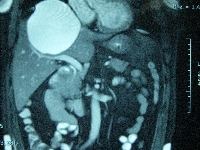

Ασθενής 61 ετών ο οποίος, στα πλαίσια διερεύνησης επιγαστραλγίας, διαπιστώθηκε ότι έπασχε από ευμεγέθη (13 cm) επικρατούσα απλή ηπατική κύστη που εδράζονταν στα ηπατικά τμήματα 4α, 5, 7 και 8 (εικόνα 1). Η κύστη παρεκτόπιζε μερικώς το δεξιό κλάδο της πυλαίας φλέβας (εικόνα 2) και εφάπτονταν με τη δεξιά ηπατική φλέβα (εικόνα 3). Ο ασθενής υποβλήθηκε σε λαπαροσκοπική (HALS) μαρσιποποίηση της ηπατικής κύστης (εικόνα 4) κατά την οποία αφαιρέθηκε > 50% του άνω και οπισθίου τοιχώματός της, μαζί με τμήμα του παρακείμενου ηπατικού παρεγχύματος (εικόνα 5). Η ταχεία ιστοπαθολογική εκτίμηση του παρασκευάσματος δεν ανέδειξε κακοήθη στοιχεία. Επιπλέον, πραγματοποιήθηκε και επιπλοοπλαστική, ύστερα από πλήρη κινητοποίηση του μείζονος επιπλόου, μεταφορά του στο δεξιό υποδιαφραγματικό χώρο και τοποθέτησή του μέσα στην υπολειμματική κυστική κοιλότητα (εικόνα 6). Ο ασθενής έλαβε εξιτήριο την 4η μετεγχειρητική ημέρα. Έκτοτε παραμένει ελεύθερος συμπτωμάτων.